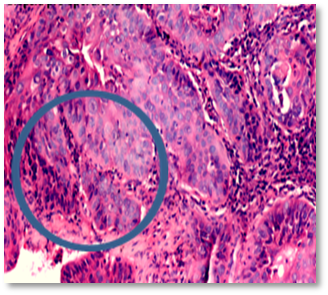

Posteriormente se recibe resultado de biopsia que reporta una neoplasia maligna epitelial con predominio escamoso (80 %), junto a islotes de diferenciación glandular incompleta, infiltrando el estroma (Figura 3y 4, flecha y óvalos azules).